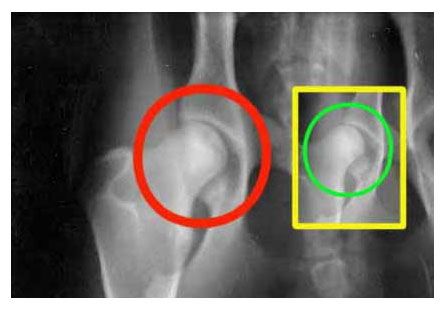

Рентген ТБС собаки. Норма

Рентген ТБС собаки. Двусторонняя дисплазия, артроз

Рентгенография является основным методом диагностики дисплазии тазобедренных суставов. При проведении рентгенологического исследования животное располагается на спине с вытянутыми тазовыми конечностями.

На рентгенограмме в зависимости от степени дисплазии (А, B, C, D, E) определяются различные рентгенологические признаки. Впервые рентгенологическая оценка ДТБС была дана в 1966 году Ортопедическим фондом животных образованным John Olin.